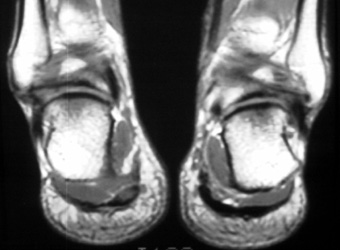

22 years old male with history of pain and tenderness in the heel of right

foot.

Coronal protein density and sagittal fast spin echo T2 W images demonstrate

focal thickening of plantar fascia and edema in the flexor digitorum brevis and

subcutaneous tissue.